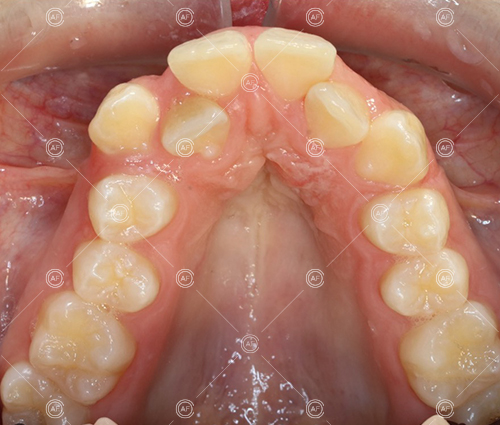

about this case…MH presented with class 1 incisors on the class 1 skeletal base with a slightly increased vertical proportion. She had severe crowding in the upper arch and moderate crowding in the lower. Due to the crowding in the lower arch, the lower centre line was off to the left by 2mm.

Buccal segments were essentially class 1 on the right hand side and a full unit class 2 on the left. This is due to buccal exclusion of the upper left 3 and mesial drift of the upper buccal segment.

- Extraction of upper right 5, upper left 4, lower left 5, lower right 5